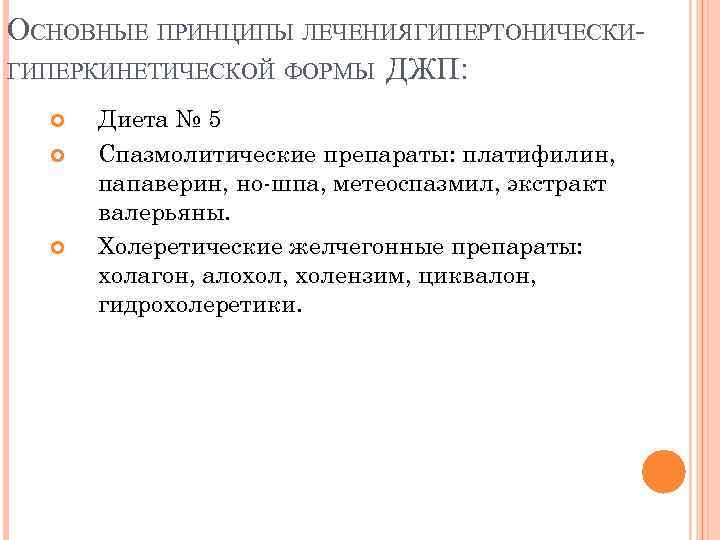

ОСНОВНЫЕ ПРИНЦИПЫ ЛЕЧЕНИЯ ГИПЕРТОНИЧЕСКИГИПЕРКИНЕТИЧЕСКОЙ ФОРМЫ ДЖП: Диета № 5 Спазмолитические препараты: платифилин, папаверин, но-шпа, метеоспазмил, экстракт валерьяны. Холеретические желчегонные препараты: холагон, алохол, холензим, циквалон, гидрохолеретики.